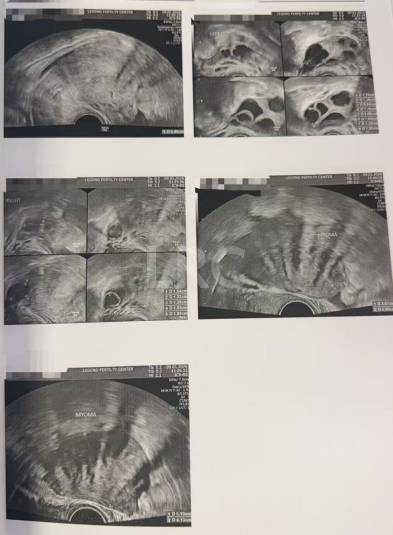

治疗结果

取卵及受精

取卵:10颗

成熟MII:10颗

ICSI受精:8颗

养囊成功:6颗

▲ Y女士的养囊报告